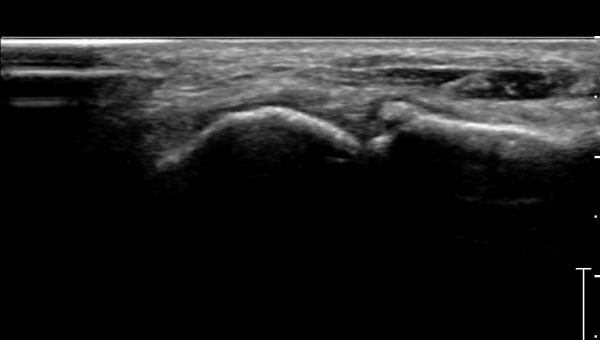

ÃÊÀ½ÆÄ°Ë»ç :  Àü°ÅºñÀδë Á¾´Ü¸é°Ë»ç¿¡¼­ Àü°ÅºñÀδëÀÇ Àú¿¡ÄÚ À§ÃàÀÌ °üÂûµÇ°í °Å°ñ °æºÎÀÇ °ß¿­°ñÀý ¹×

°Å°ñÁÖ»ó°ñ°üÀý ºÎÁ¾ÀÌ °üÂûµÈ´Ù(»çÁø 1).